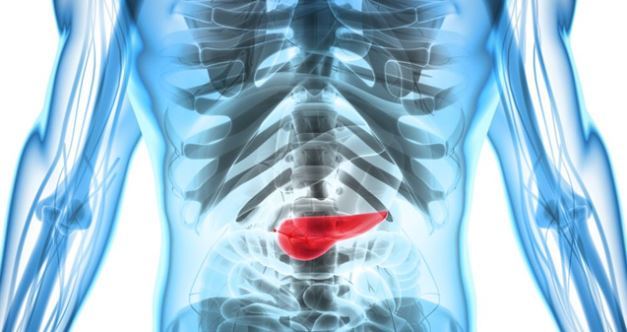

췌장암이란

췌장암은 조기 발견이 가장 어려운 암 중 하나로 알려져 있습니다. 위치상 주변에 중요한 혈관이 얽혀있고, 암 발생 시 전이 위험도 매우 높은 것으로 알려져 있어 다른 암에 비해 진단이 쉽지 않고 치료도 쉽지 않아 실제 진단을 받았을 때는 이미 수술적 치료가 늦은 경우가 많은 것으로 알려져 있습니다.